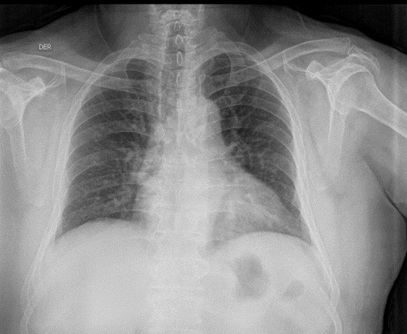

La radiografía de tórax sin patología pulmonar, mediastino normal, cardiomegalia grado I. (Ilustración 2)

Ilustración 2 Radiografía de tórax

Fuente: Hospital de Especialidades Guayaquil “Doctor Abel Gilbert Pontón”.